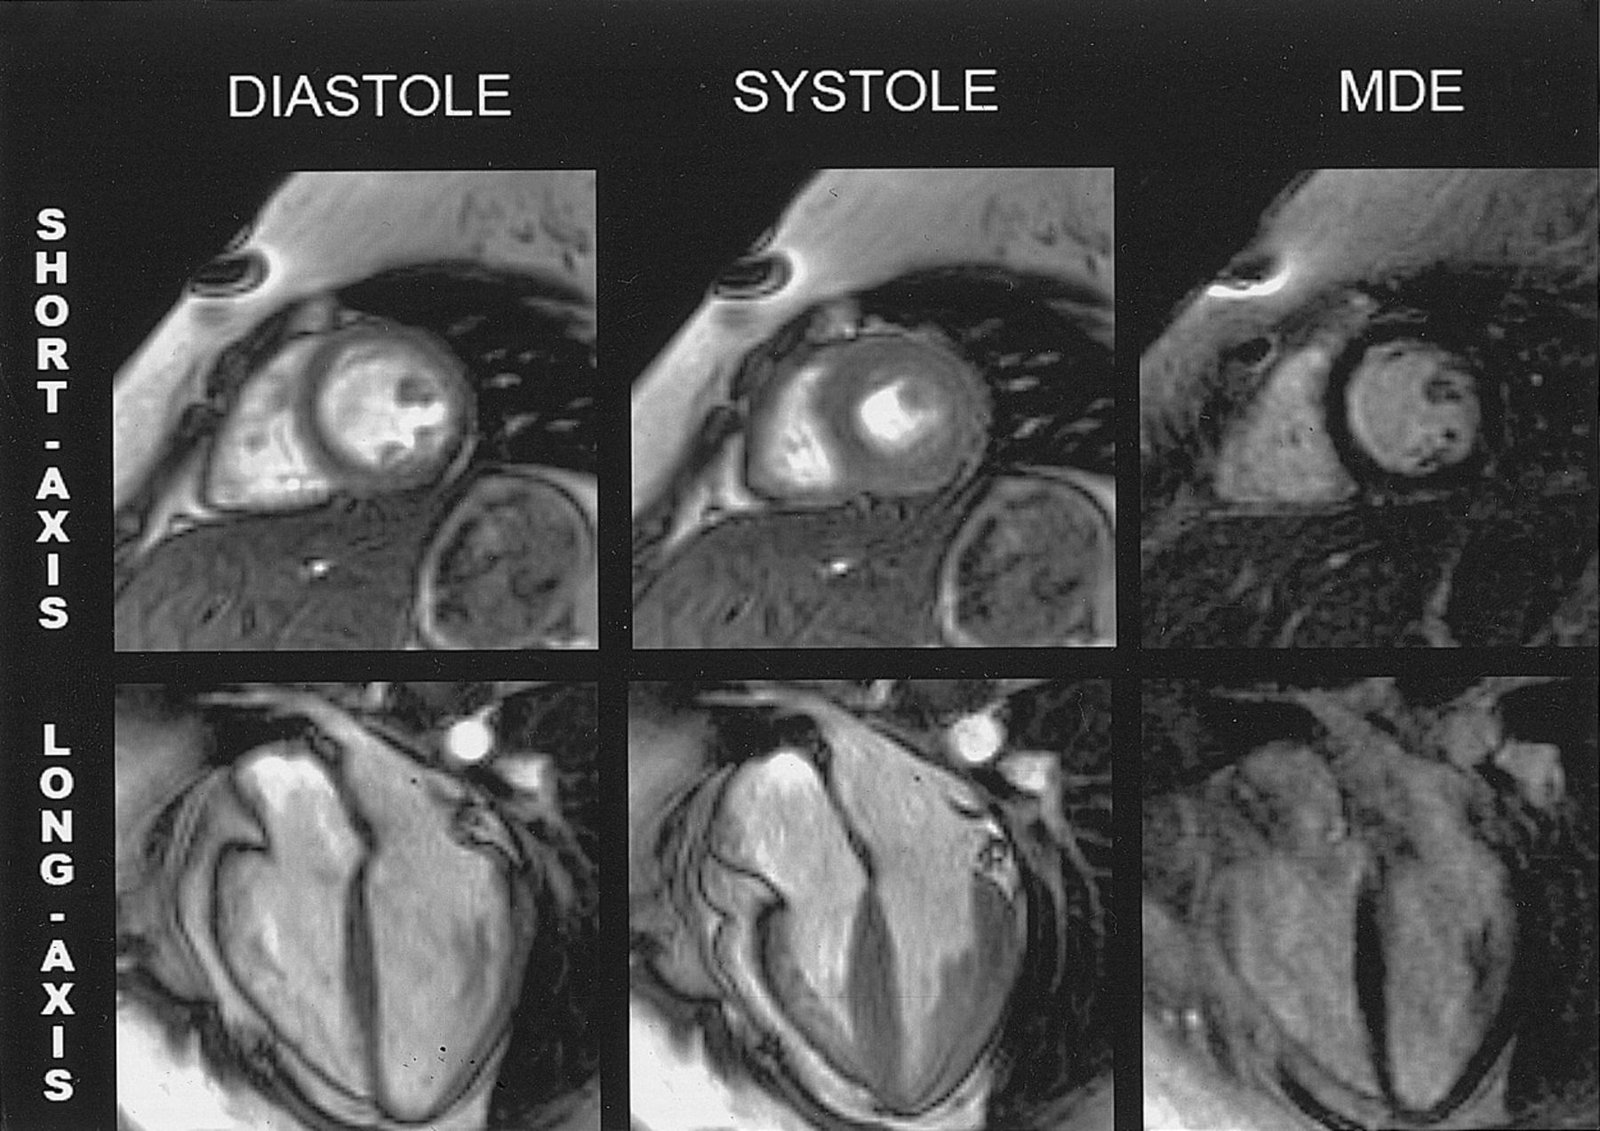

CARDIAC MRI

A cardiac MRI uses magnetic fields and radio waves to create detailed images of your heart. This test may be used to determine the severity of your condition and assess the size and function of your heart chambers (Atria & ventricles).